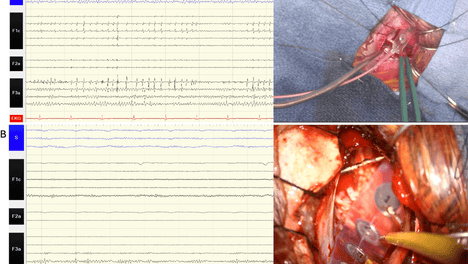

【神外早8点 手术有新译】经眉弓切口眶上锁孔开颅术联合立体脑电图电极引导治疗局灶性额叶癫痫一例

对于病灶位于相似解剖区域(如额极、眶额区)的患者,该入路应作为重点考虑方案,其独特优势在于,能在开放性手术中让sEEG电极保持原位,即便与传统入路相比暴露范围更小,仍可通过电极提供的解剖定位信息和电生理数据,…